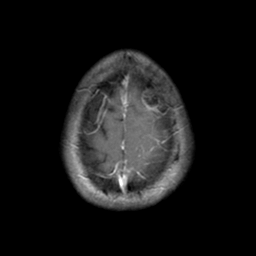

Sarcoma, MR Study #1 mr-gad -- Slice #22

[Home][Help][Clinical] Slice 22